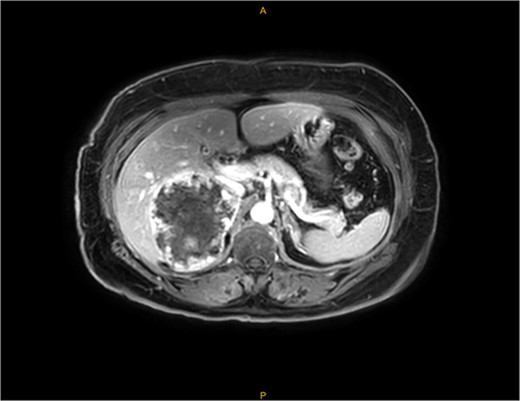

An MRI scan with gadolinium was arranged, demonstrating a complex right adrenal mass (9.8 × 8.2 × 8.1 cm). There was heterogeneous T1 and T2 signal with nodular peripheral enhancement and progressive filling-in (Fig. 2), suggestive of a giant adrenal haemangioma. A PET scan further demonstrated a photopenic mass with a mild peripheral rim of FDG accumulation (SUV max 3.4) (Fig. 3). The appearances did not suggest high-grade malignancy. A red cell scan did not identify progressive accumulation on delayed imaging, atypical for a haemangioma.

MRI—demonstrating peripheral enhancement in large, complex right-sided adrenal lesion (9.8 × 8.2 × 8.1 cm).